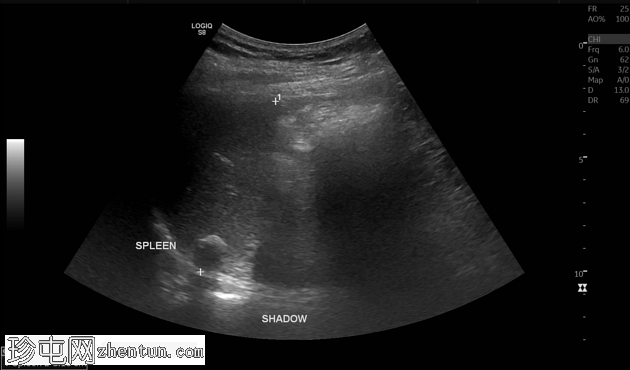

超声

纵切面

脾脏大小正常,纵轴约8.15厘米。脾实质内可见一孤立、边界清晰的高回声灶,符合钙化表现。该钙化灶后方可见声影,未见相关肿块、囊肿或血管异常。无脾周积液或脾肿大。

其余上腹部结构未见异常。